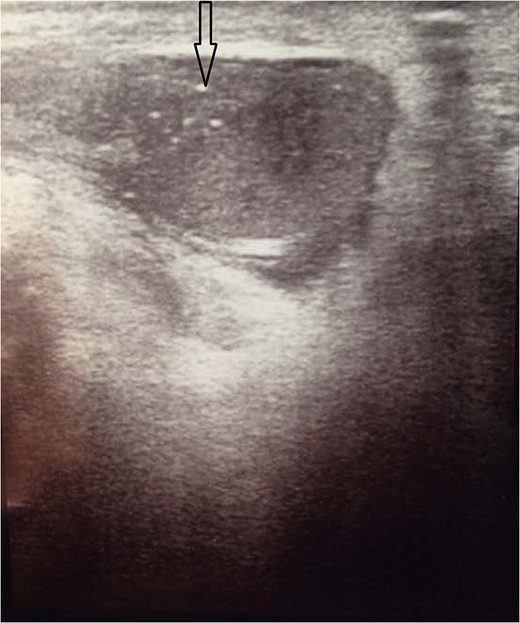

This is a 39-year-old healthy male patient with history of left undescended abdominal testis that was managed at the age of 7 years by left orchiopexy. The left testis was fixed at the external ring and was planned for second stage orchiopexy, but the patient was lost to follow up. At 39 years of age, the patient presented with localized severe left hemiscrotal and inguinal pain of one day duration. Physical examination demonstrated a fixed testis at the left external inguinal ring with marked hardness of the surrounding paratesticular tissue. A brief course of oral antibiotics for suspected left epididymo-orchitis failed to improve his symptoms. Laboratory tests showed ß-HCG: <1.2 mIU/ml (reference range: 0–4 mIU/ml); alfa-fetoprotein: 1.39 ng/ml (reference range: ≤7 ng/ml); and LDH: 247 U/l (reference range: 135–225 U/l). Testicular ultrasound revealed a small left testis of heterogeneous echotexture and measuring 2.8 × 1.7 cm2 and it contained multifocal calcifications (Fig. 1). It was located high in the scrotal sac at the end of the inguinal canal. There was inflammation and swelling of the left spermatic cord.

Ultrasound of the testicles showed very small atrophic left testis measuring about 2.8 × 1.7 cm2 with multiple calcifications within it (black arrow).